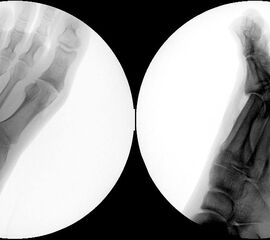

Klinisch zeigt sich stadienabhängig eine schmerzhafte Bewegungseinschränkung mit zunehmender Steifigkeit des Großzehengrundgelenkes. Vor allem die Einschränkung der Dorsalextension wird von den Patienten oft als unangenehm empfunden. Initial besteht eine bindegewebige Alteration im Gelenk, im weiteren Stadium treten Knorpeldegeneration und Begleitsynovialitis mit der Ausbildung von osteophytären Randanbauten auf. Klinische treten diese meist durch eine schmerzhafte dorsale Knochenkante in Erscheinung (Abbildung 1).

Im späten Stadium imponiert eine Gelenkblockierung durch freie Gelenkkörper. Während in den Anfangsstadien vor allem die dorsalen Anteile des Gelenks betroffen sind, betreffen die Veränderungen in den Fortgeschrittenen Stadien die gesamte Zirkumferenz einschließlich des Sesambeingleitlagers. Im Endstadium kommt es zu einer weitgehenden Ankylosierung des 1. Metatarsophalangealgelenks.

• Röntgenaufnahme des Fußes in drei Ebenen unter Belastung